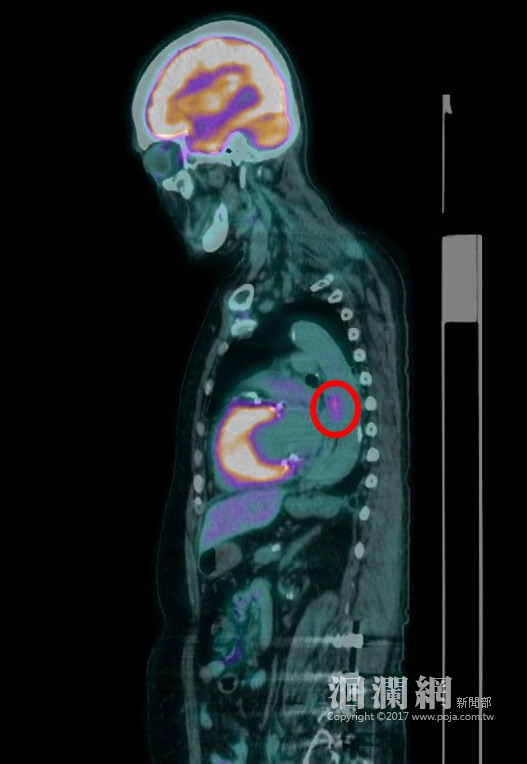

除了一般健康檢查的方式,近年來隨著醫療技術的精進,正子掃描也成為健康檢查的利器,門諾醫院核醫科主任游冬齡表示,目前包括肺癌、大腸直腸癌、頭頸癌、淋巴癌、食道癌、黑色素瘤、甲狀腺癌、乳癌及子宮頸癌等,都可藉由正子攝影找出癌細胞,且準確率在9成以上。雖然正子掃描會使用到放射性物質,門諾醫院使用的是最新型的低劑量正子掃描儀,優點是靈敏度高,因此正子藥物劑量可減少70%以上,因此輻射量也大幅減少70%以上,輻射量其實是很微量的。

醫師強調,正子掃描是全身性的掃描,非侵入性的檢查,除了可以節省時間外,也可減少部分檢查對患者帶來的風險與不安,減緩因檢查而造成的不適,提升檢查舒適度。建議50歲以上有家族癌症史、有抽菸、飲酒、吃檳榔以及愛吃燒烤、刺激性食物、生活型態長期不正常…等癌症高危險群的民眾,透過正子掃描,為自己的健康做進一步把關。

雖然正子掃描還是有檢查死角,但相較於其他傳統的檢查方式,正子掃描對於癌細胞的分辨準確度已相當高,民眾如有疑慮,可另外搭配其他相關檢查,如胃鏡、肝臟超音波等深入型檢查,讓癌症早日現形,早期治療。